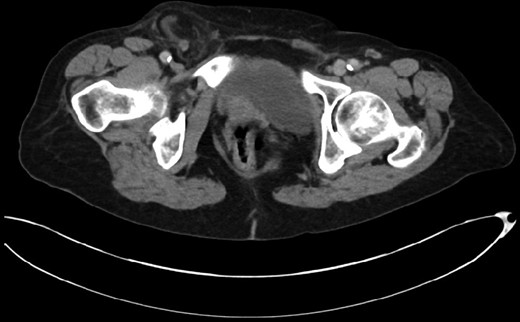

This 82-year-old lady presented with a sudden painful right sided groin swelling not previously noticed. She had no features of obstruction and was opening her bowels and not vomiting. Her medical background included left sided femoral hernia repair in 2005, coronary artery bypass graft and bilateral total knee replacements. On examination her abdomen was soft with the presence of a tender, irreducible swelling in the right groin, inferolateral to the pubic tubercle. She had good bowel sounds and there was stool present in the rectum on PR examination. A full set of blood tests demonstrated no abnormality. A CT abdomen and pelvis demonstrated an incarcerated right sided femoral hernia containing an 8 mm long inflamed appendix with a small amount of localized free fluid and inflammation indicative of De Garengeot’s hernia with underlying acute appendicitis (Fig. 1). The hernia sac diameter measured 2 mm on CT scan. She was taken to theatre for an open Lockwood repair of her femoral hernia and an appendicectomy. Following an initial Lockwood incision over the lump, dissection was performed down to the hernia sac also exposing the inguinal ligament (Fig. 2). The tightness of the femoral ring made mobilization of the appendix difficult. By partially incising the inguinal ligament superior to the femoral ring, the appendix was freed, and on inspection showed inflammation particularly towards the tip (Fig. 3). The caecum was then reduced and the inguinal ligament was repaired with non-absorbable suture. The femoral hernia was then repaired with a small funnel of ultrapro mesh. Appendicectomy was then performed in the usual fashion via the Lockwood incision leaving a slightly longer stump than usual (Fig. 4).

De Garengeot’s hernia – femoral hernia sac containing the vermiform appendix.